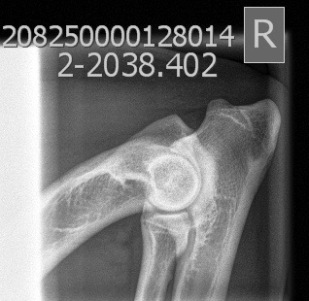

HD: A/A

AD: 0/0